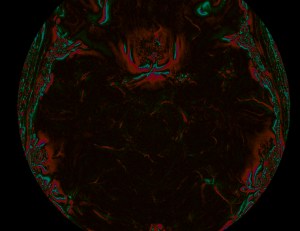

Suceptablity differences between tissues can and phase changes to the images we acquire. Here the sinus cause a beautiful rose-shaped pattern